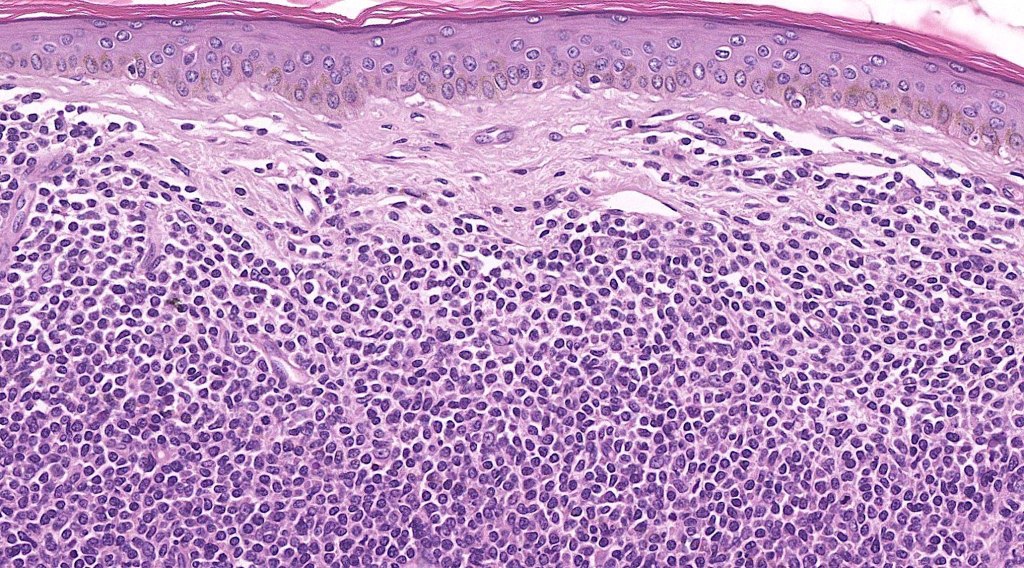

. No epidermal involvement

. Dermal +/- subcutaneous fat infiltrate

. Monotonous blast cells with gray-blue cytoplasm & irrregular vesicular nuclei with prominent nucleoli